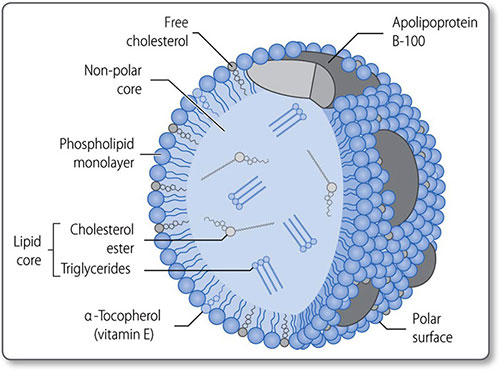

Cholesterol metabolism

Cholesterol is a 27-carbon steroid alcohol (sterol) lipid (Figure 1.45). It is a key component of cell membranes, allowing their fluid movement, and is the precursor to vitamin D, bile acids and steroid hormones, including testosterone and cortisol.

Cholesterol is consumed in the diet and synthesized de novo in the liver and intestine. On average, 800 mg of cholesterol is synthesized daily in a person on a low-cholesterol diet.